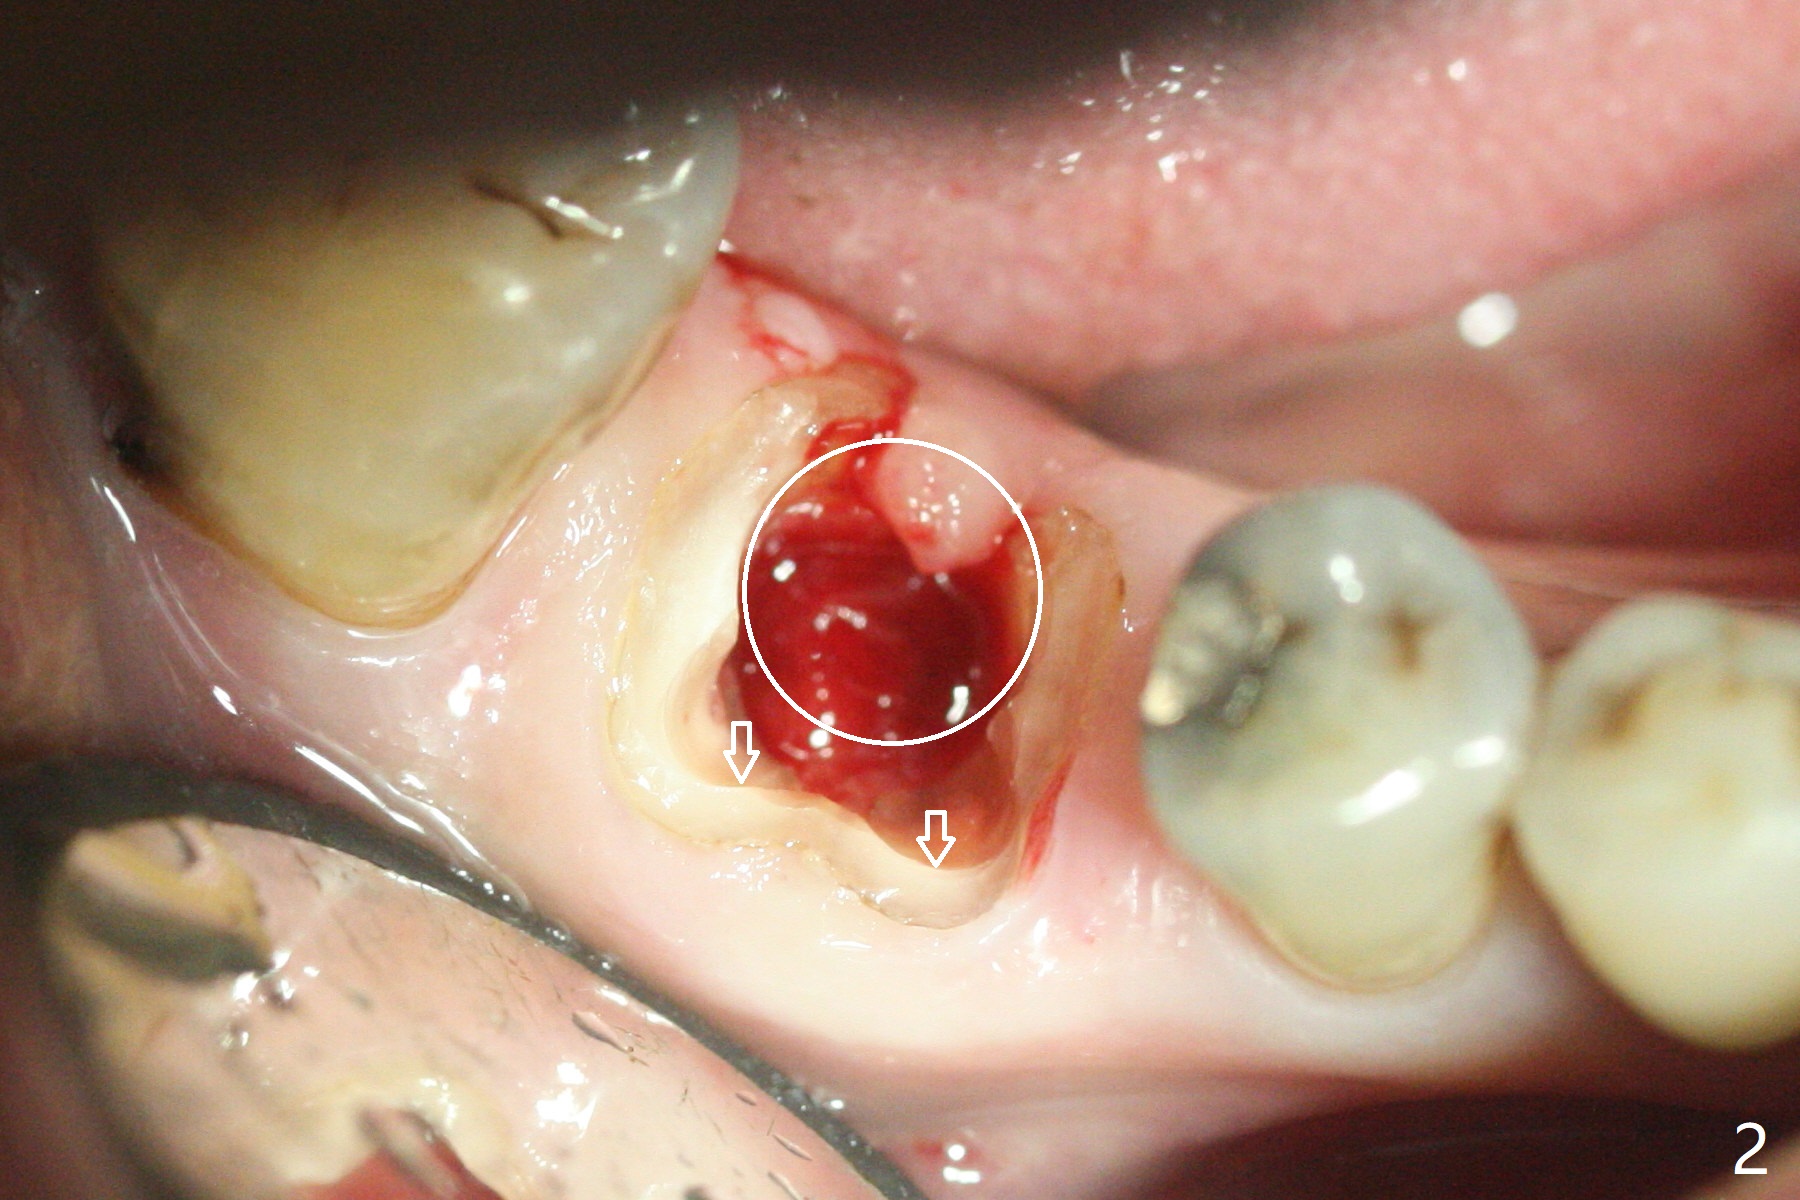

As planned, the crown of the tooth #30 with lingual (Fig.1 L) caries is removed and flattened with surgical handpiece so that the guide is able to be seated without interference. The osteotomy by 10.5 mm offset bone trimmer is lingual (Fig.2 white circle; due to in part the lingual caries and in part design error); in order to let the osteotomy to bounce back buccal, the part of the buccal roots are removed by surgical bur (arrows). The initial osteotomy by 2.2 mm drill is in the middle of the septum (Fig.3). After the last drill (3.5x11.5), the remaining roots are easily removed with proximators; a 4x11 mm dummy implant is placed with low stability and supracrestal lingual (Fig.4). Therefore a 4.5x9 mm final implant is placed with low torque. Following 4x11.5 mm drill, the torque increases to 20 Ncm. With insertion of healing screw, sticky bone (Fig.4 *: .5-1 mm cortical/cancellous allograft) is heavily packed around the implant (arrow), which apparently allows removal of the healing screw and placement of a 6x5.7(3) mm pair abutment without loosening the underlying implant. More bone graft is placed (Fig.6), followed by 2 pieces of PRF membranes. Although the implant is slightly buccally placed (Fig.7, due to over-removal of the buccal root, Fig.2 arrows), it is placed in the septum (Fig.8 S). To further compensate for the low implant stability, setting acrylic is applied in the edentulous area, particularly into the undercuts of the neighboring teeth (Fig.9 *) and around the abutment. The lingual margin of the acrylic dressing is extended (Fig.10 arrow) to cover the soft tissue defect associated with the lingual caries. As compared to the design (4x10 mm, Fig.11), the implant (4.5x9 mm, Fig.12) is placed buccal and ~ 2 mm deeper, reducing the chance of periimplantitis. The acrylic dressing is in place, but has mobility. The gingiva is healthy 2 weeks postop. The dressing is removed 1 month postop; the socket heals around the abutment buccal (Fig.13) and lingual (Fig.14). In spite of the immediate provisional, the abutment margin is substantially subgingival mesial 4 months postop, extremely difficult to take impression. A smaller diameter and longer cuff abutment is placed (Fig.15). The lingual gingiva heals normal 5 months postop, immediately before cementation (Fig.16).